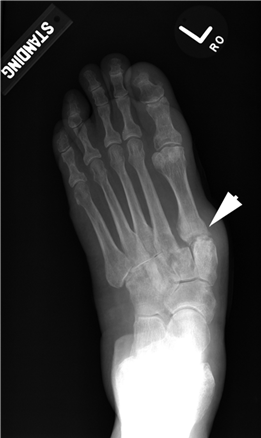

Weight-bearing anteroposterior (AP), lateral, and sesamoid axial radiographs are mandatory. On the AP view, the surgeon measures the Hallux Valgus Angle (HVA, normal < 15°), the Intermetatarsal Angle (IMA, normal < 9°), and the Distal Metatarsal Articular Angle (DMAA). The lateral view is scrutinized for Meary's angle (talo-first metatarsal angle) to identify midfoot collapse, as well as the presence of dorsal osteophytes indicative of hallux rigidus. The sesamoid axial view is critical for assessing the degree of sesamoid subluxation and the integrity of the crista.

Clinical & Radiographic Imaging Archive